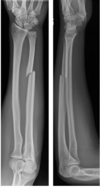

Monteggia vs. Galeazzi

Galeazzi = distal radius fracture + distal radio-ulnar dislocation

Monteggia = proximal ulna fracture + radial head dislocation